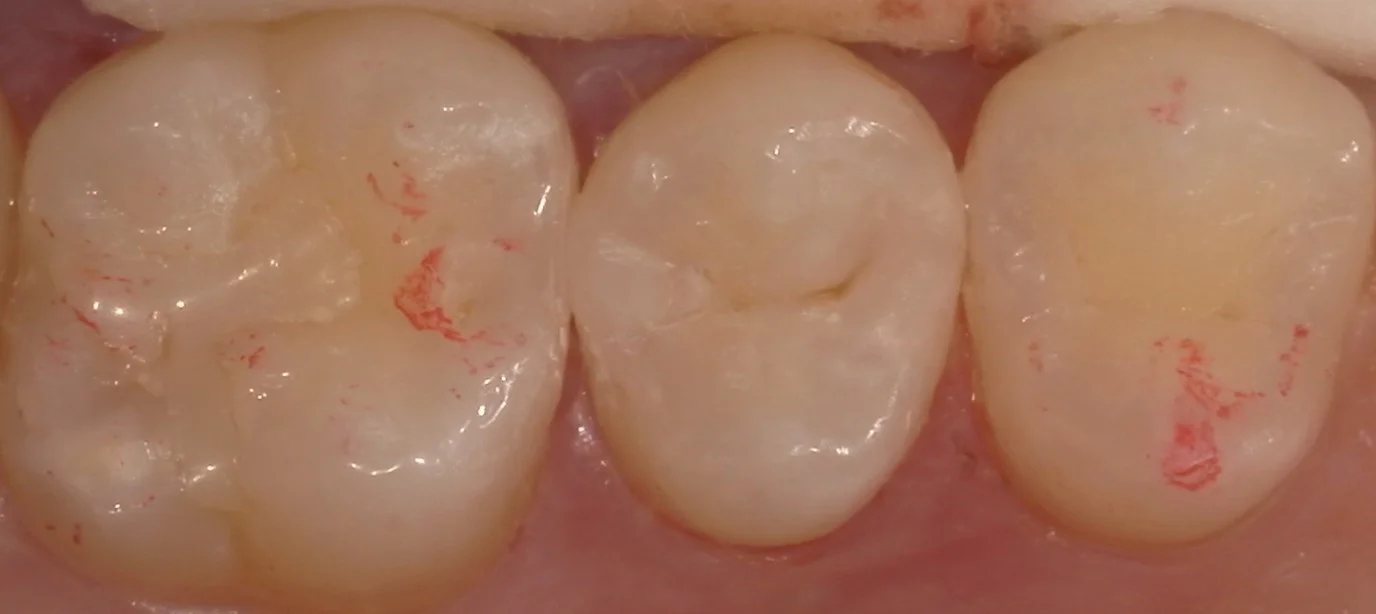

そして詰め終わったのがこの状態です。

違和感なく仕上げられたかと思います。

患者さん自身、喜んでいただけました。

また余談ですが、この方は日ごろの定期健診を行う医院を新しく見つけ、かかった所、そちらの歯科医師からも綺麗だと言って頂けたようです。

しっかりとケアしてなるべく長く使っていただければ幸いです。